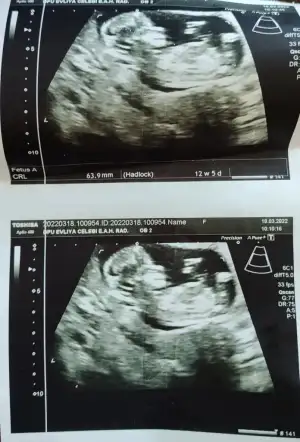

10 haftalık karından bakıldı banada tahminde bulunurmusunuz

Eklentiler

• 7ADF28E5-4760-438C-8238-06FCEFA0193E.webp

7ADF28E5-4760-438C-8238-06FCEFA0193E.webp

48,7 KB · Görüntüleme: 69